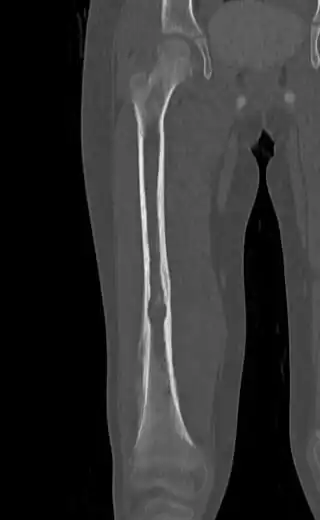

Medical imaging

On conventional radiographs, the most common osseous presentation is a permeative lytic lesion with periosteal reaction.[1] The classic description of lamellated or "onion-skin" type periosteal reaction is often associated with this lesion.[1] In addition, Magnetic resonance imaging (MRI), Computed axial tomography (CT) and PET scan can help fully define the Ewing sarcoma and assess any spread.[1]

MRI will show the full bony and soft tissue extent and relate the tumor to other nearby anatomic structures (e.g. vessels). Gadolinium contrast is not necessary as it does not give additional information over noncontrast studies, though some current researchers argue that dynamic, contrast-enhanced MRI may help determine the amount of necrosis within the tumor, thus help in determining response to treatment prior to surgery. Computed axial tomography (CT) can also be used to define the extraosseous extent of the tumor, especially in the skull, spine, ribs, and pelvis. Both CT and MRI can be used to follow response to radiation and/or chemotherapy. Bone scintigraphy can also be used to follow tumor response to therapy. In the group of malignant small round cell tumors that includes Ewing sarcoma, bone lymphoma, and small cell osteosarcoma, the cortex may appear almost normal radiographically, while permeative growth occurs throughout the Haversian channels. These tumors may be accompanied by a large soft-tissue mass while almost no bone destruction is visible. The radiographs frequently do not shown any signs of cortical destruction. Radiographically, Ewing's sarcoma presents as "moth-eaten" destructive radiolucencies of the medulla and erosion of the cortex with expansion.